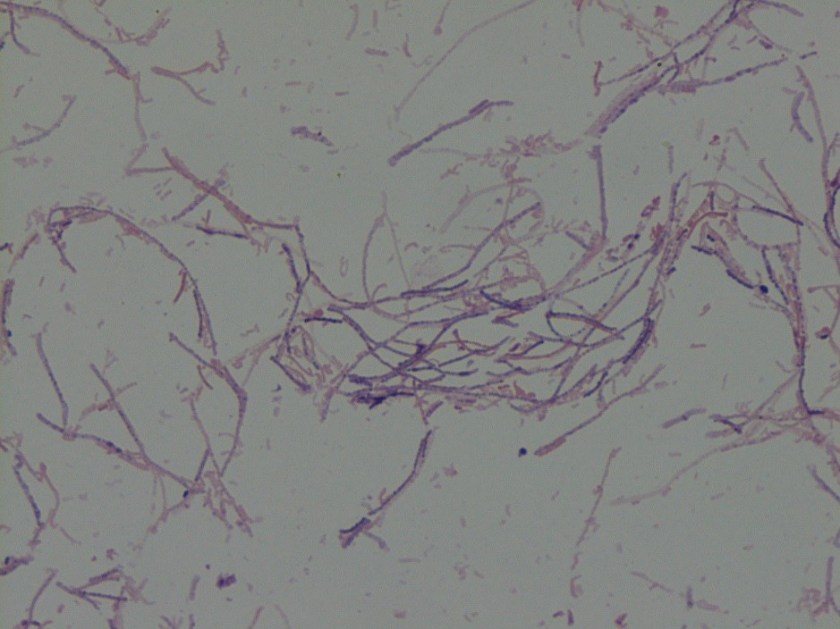

Initial Gram stain showed few polymorphonuclear leukocytes with no bacteria seen. Cell count was unable to be performed due to viscosity of the specimen but differential showed 80% neutrophils. There was no growth on aerobic blood, chocolate, or MacConkey agars. Anaerobic Schaedler (non-selective) agar grew 1-2 mm brownish colonies (Image 1). Gram stain of this isolate revealed gram variable bacilli forming long filaments (Image 2). The isolate was identified using MALDI-TOF MS (Vitek) as Clostridium ramosum.

Clostridium species are anaerobic, spore-forming, gram positive bacilli. C. ramosum is non-motile and is normally found in the human colon and the environment. One study identified C. ramosum in the feces of 83% of sampled adults. Former names include Eubacterium filamentosum, Ramibacterium ramosum, Actinomyces ramosus, and Eubacterium ramosum. Figure 2 demonstrates a notable characteristic of C. ramosum, i.e. its variable appearance on Gram stain. The morphology here may be described as gram negative or “over-decolorized”, though gram positive bacilli are clearly seen forming many of the filaments. Its terminal endospores are often difficult to identify on Gram stain and this is true of Figure 2. These characteristics on Gram stain have historically made identification difficult, though use of MALDI-TOF MS facilitated identification in our case. Biochemically, C. ramosum ferments glucose and hydrolyzes esculin; it is negative for lecithinase and lipase.